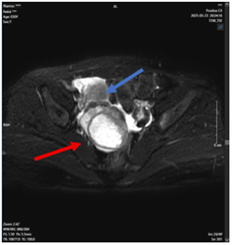

ĐAU TRONG UNG THƯ DI CĂN XƯƠNG

Hệ xương là vị trí phổ biến thứ ba cho di căn ung thư, chỉ sau phổi và gan. Nhiều bệnh lý ung bướu như ung thư vú, tuyến tiền liệt, phổi và thận, có khuynh hướng di căn mạnh mẽ đến xương, gây đau, tăng canxi máu, gãy xương bệnh lý, chèn ép...